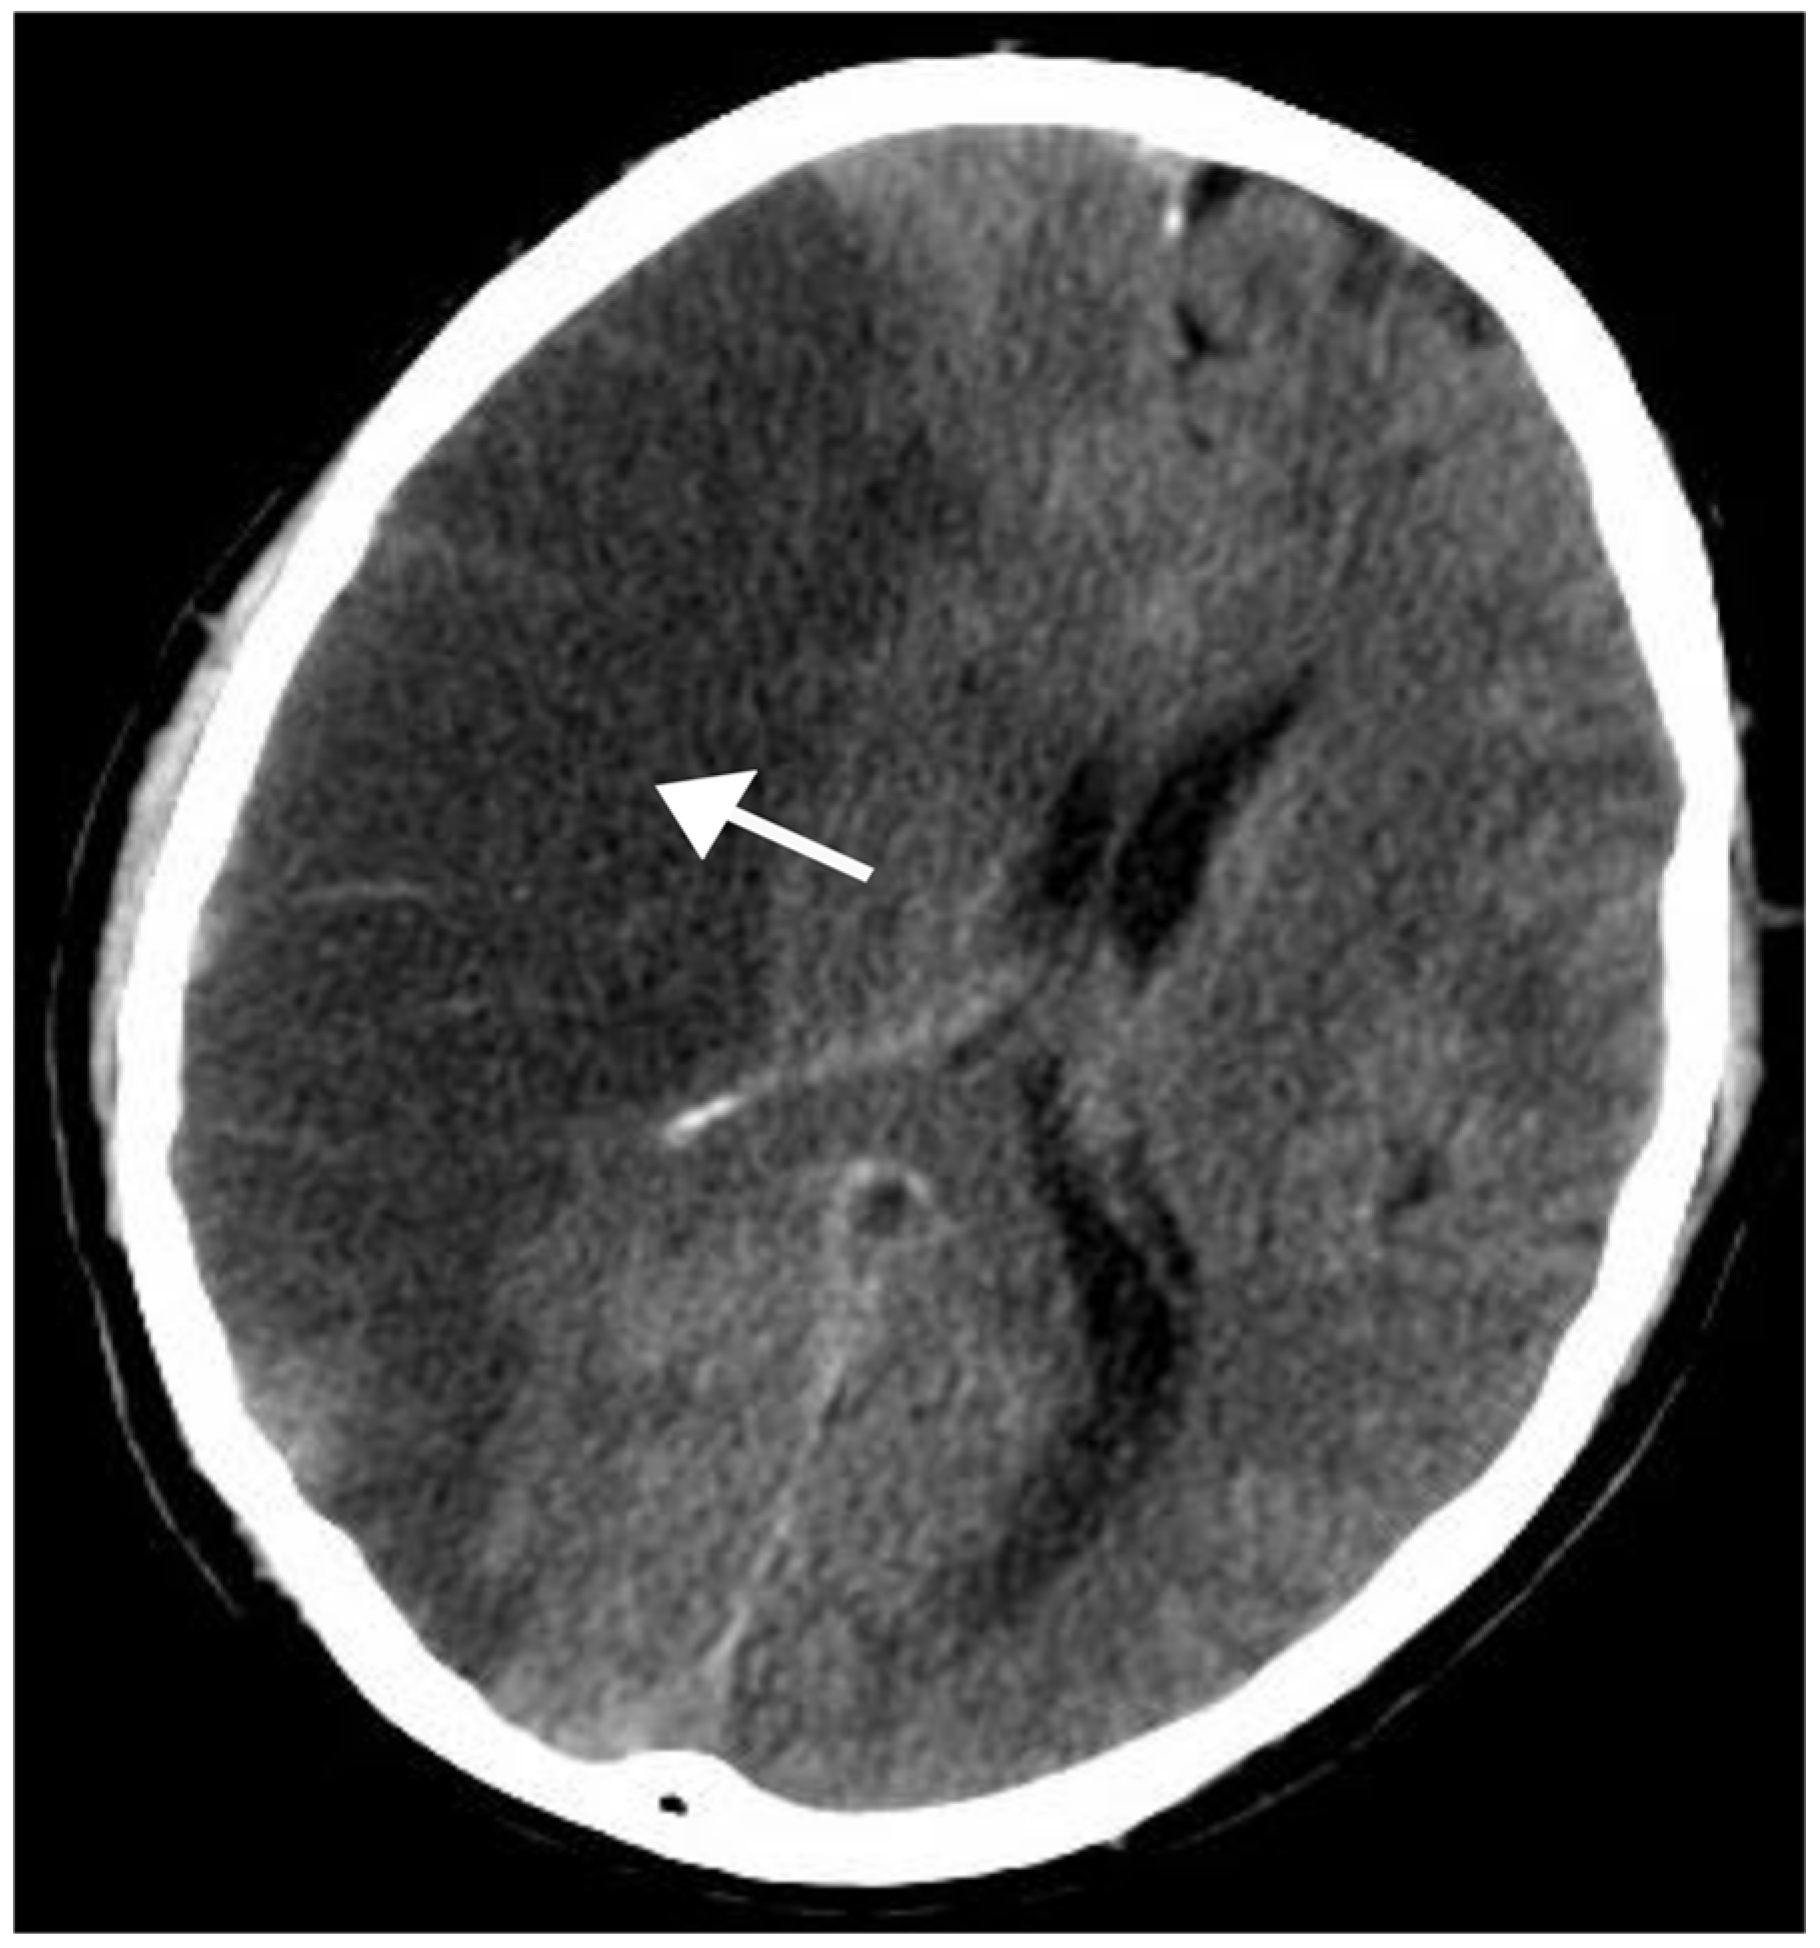

Case 5: A 61-year-old man with a complaint of left-sided hemiplegia for 4 hours,

presented to the clinic with altered sensorium

CT scans show a large hypodensity involving the entire right frontoparietotemporal lobe, insular cortex, putamen and internal capsule.

ASPECTS MCA- 3, ASPECTS PCA- 10

The patient was admitted to the ICU, intubated for 5 days with no improvement and expired on day 5 of admission.

Figure 5. NCCT of case 5.